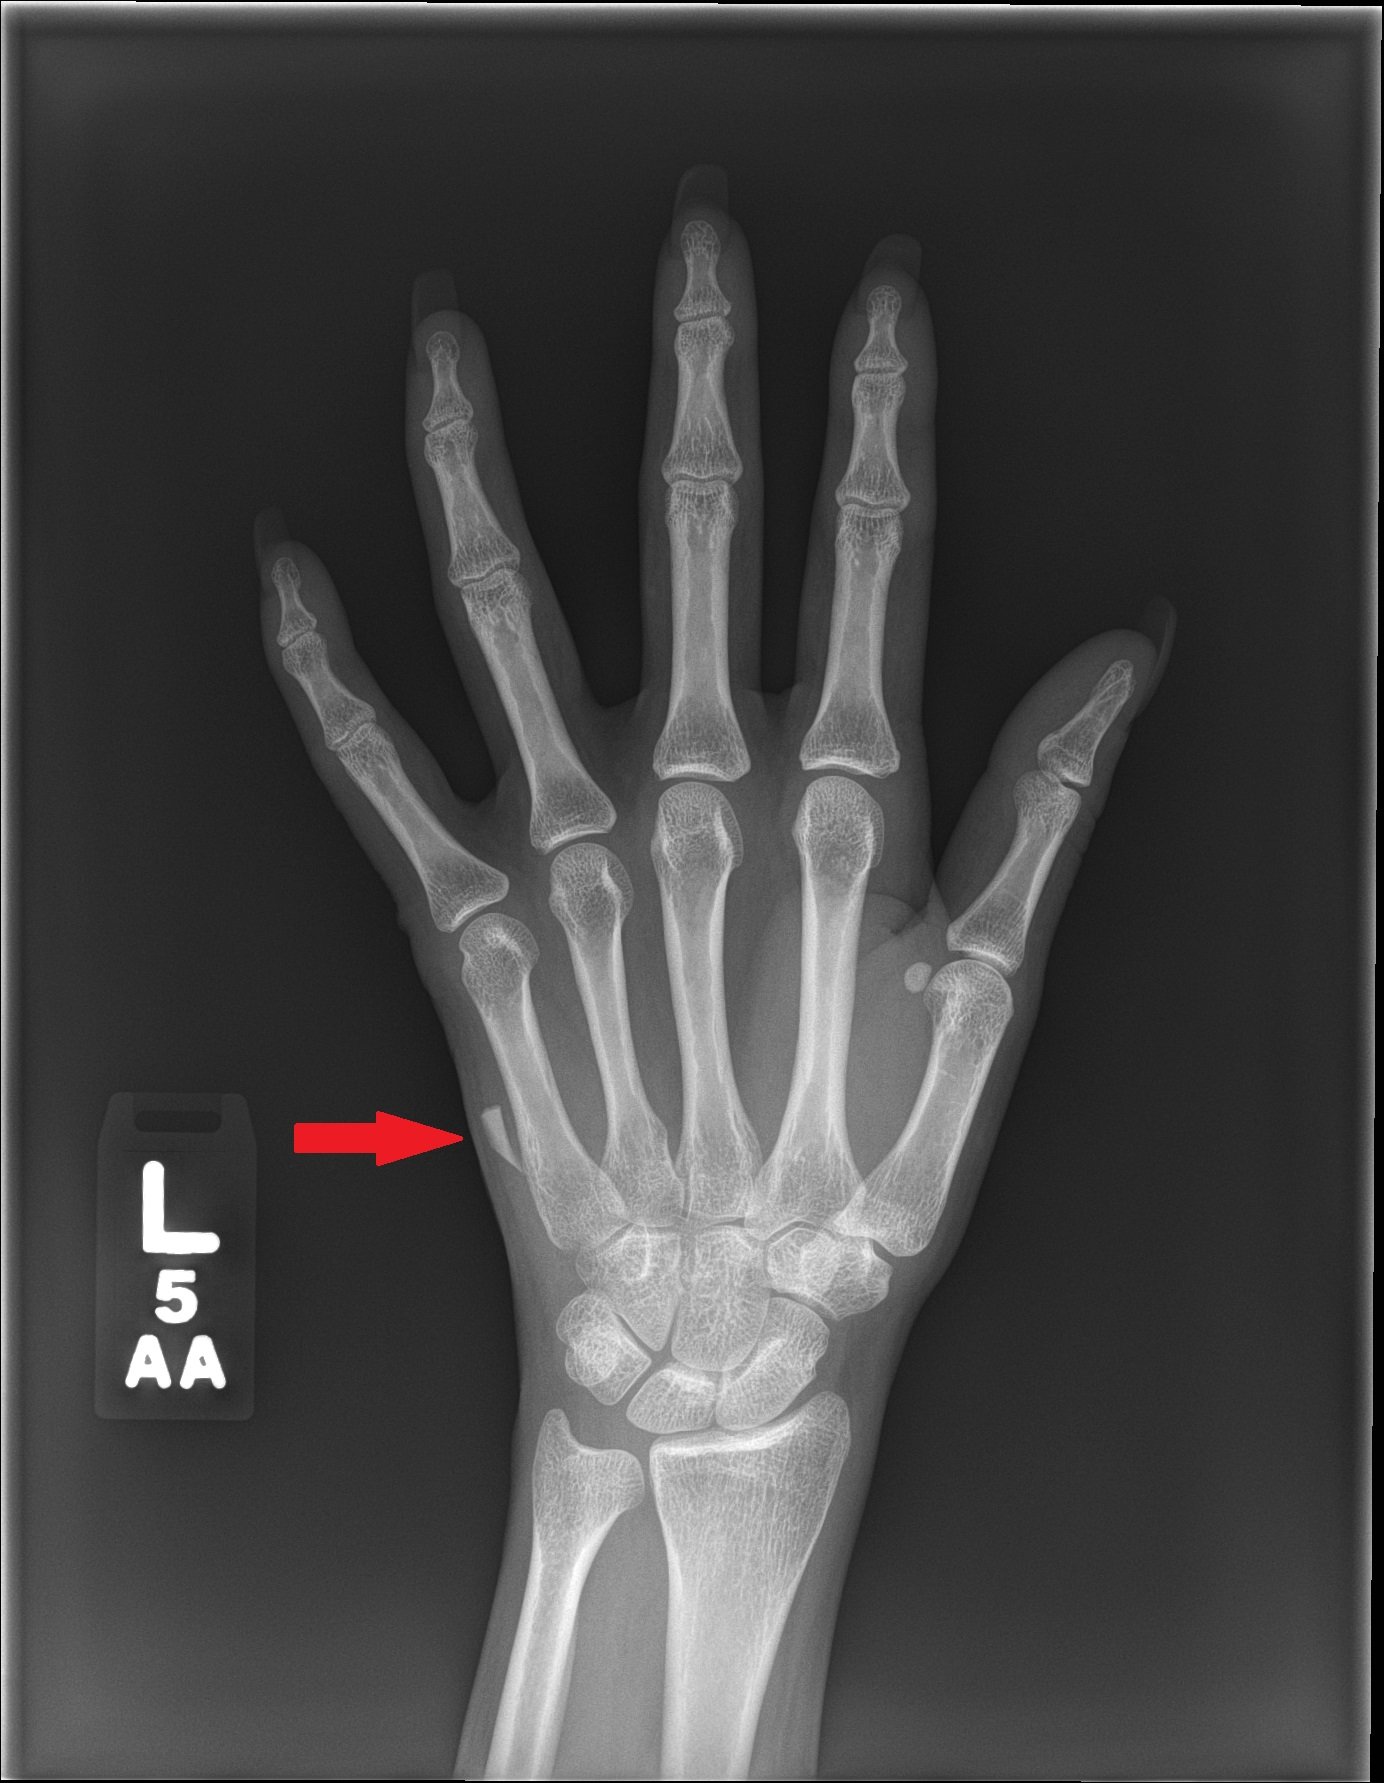

Glass Foreign Body Hand Radiograph

Significant findings:

Left hand plain radiography demonstrated a subcutaneous foreign body medial to the 5thmetacarpal that is radiopaque, trapezoidal in shape, and measures approximately 11mm x 3mm.